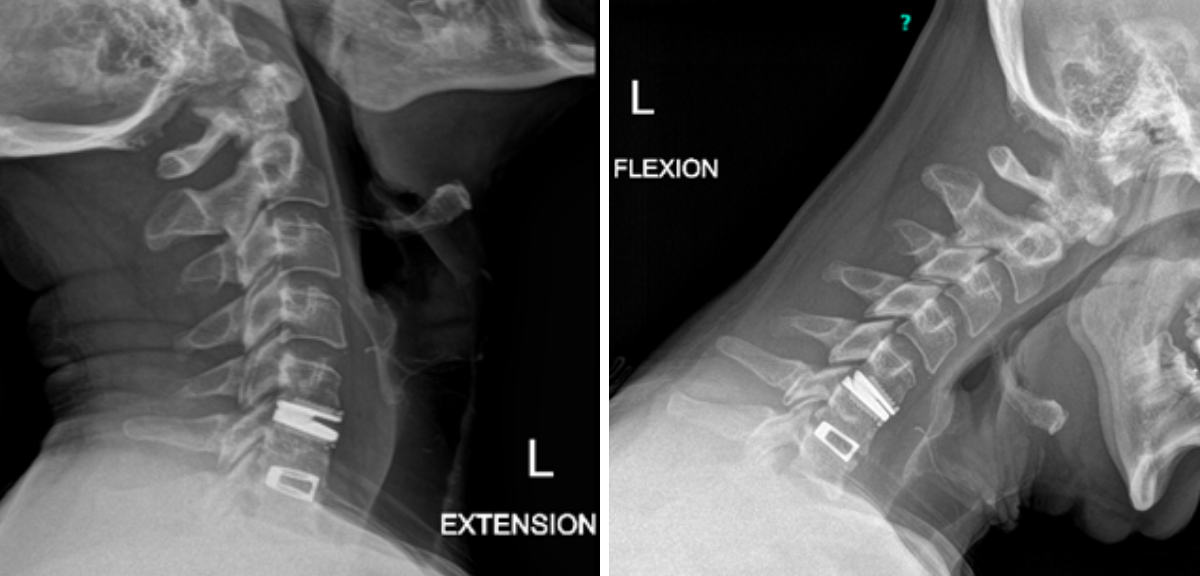

Figure 1B,C: Pre-operative CT images.

Prior to shunting, a head CT was obtained and the head CT in addition to documenting a patten of obstructive hydrocephalus suggested a possible mass lesion compressing the aqueduct at its inferior aspect. Figure #1 demonstrates the hydrocephalus and the possible lesion. A decision was made at this point that the patient had obstructive hydrocephalus that was now symptomatic and he was taken for a laparoscopic-assisted ventriculoperitoneal shunt.